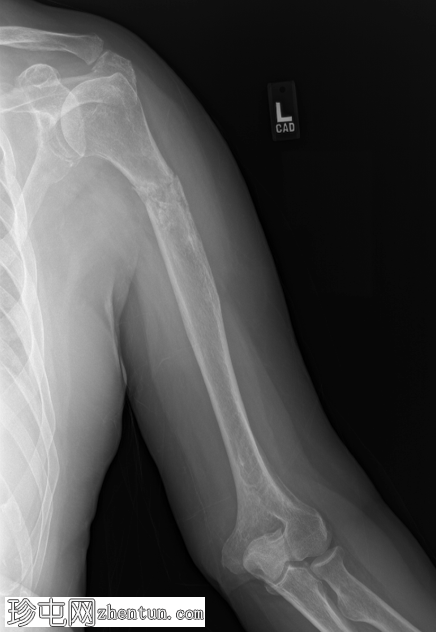

X线片

术后X线片显示病理性骨折已行髓内钉固定。